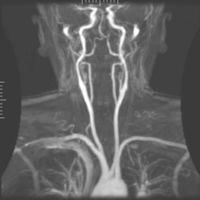

تصوير الأوعية بالرنين المغناطيسي